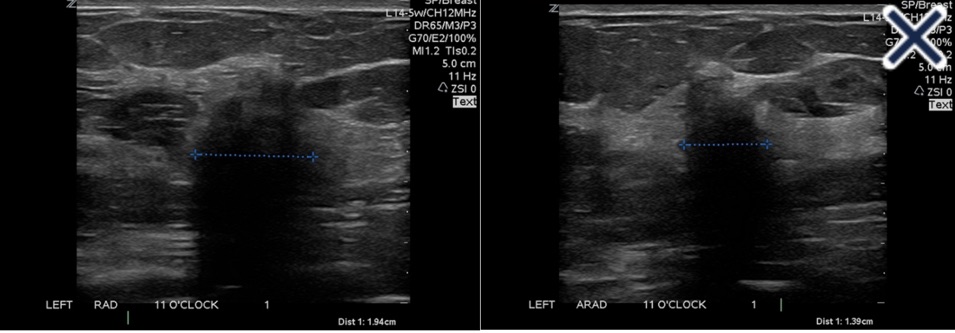

• The suppression of speckle artifact by coded harmonics makes solid nodules more hypoechoic and conspicuous than they are with fundamental imaging (Images a and b)

A. Infiltrating ductal carcinoma with fundamental imaging.

B. The same infiltrating ductal carcinoma as 2a with coded harmonic imaging.